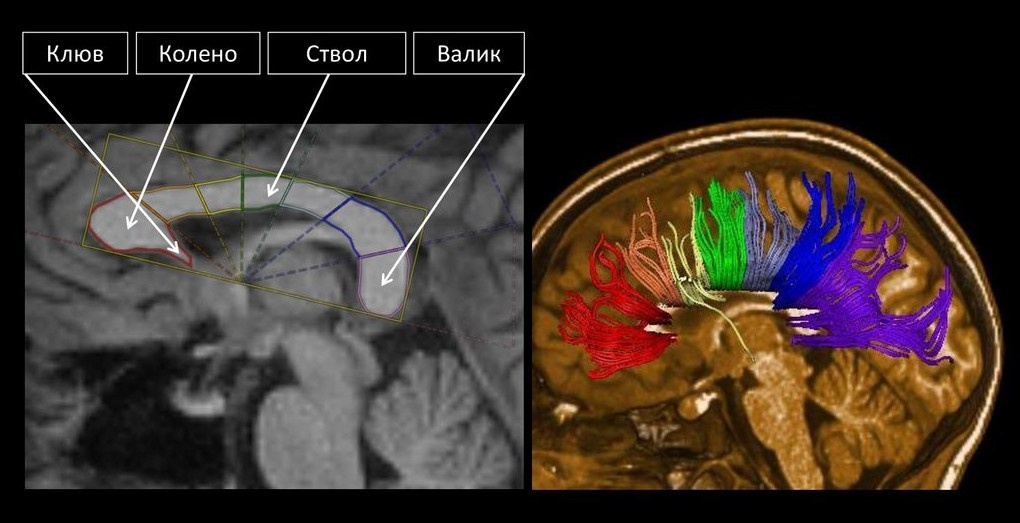

Анатомия мозолистого тела в сагиттальной проекции на МРТ крупным планом и 3D-реконструкция

Если очень просто, то это миллионы нервных волокон, соединяющих два полушария головного мозга, а основной функцией их является передача информации от одного полушария к другому, что обеспечивает слаженную их работу.

Мозолистое тело принимает непосредственное участие в координации движений, обработке речи, памяти и обеспечивает визуально-пространственную связь (например, передает "зрительную" информацию с правого полушария на "смысловую" левого при чтении).